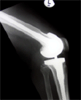

Post

Op

Post Operation Xrays of limb

Patient had restoration of limb alignment and relief of knee pain